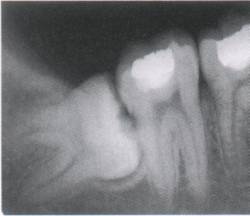

主要包括牙槽外科手术(含各种牙齿的拔除、牙槽骨修整手术、牙种植术等),口腔颌面部炎症及颞下颌关节疾病的诊断与治疗,口腔颌面部创伤(含颌面部软组织创伤及骨折)的诊断与治疗,口腔颌面部及唾液腺(腮腺、颌下腺、舌下腺)肿瘤的诊断与治疗等。